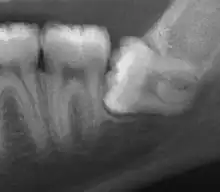

| Impacted wisdom tooth with a horizontal orientation | |

| Diagnostic method | X-rays, CT scans |